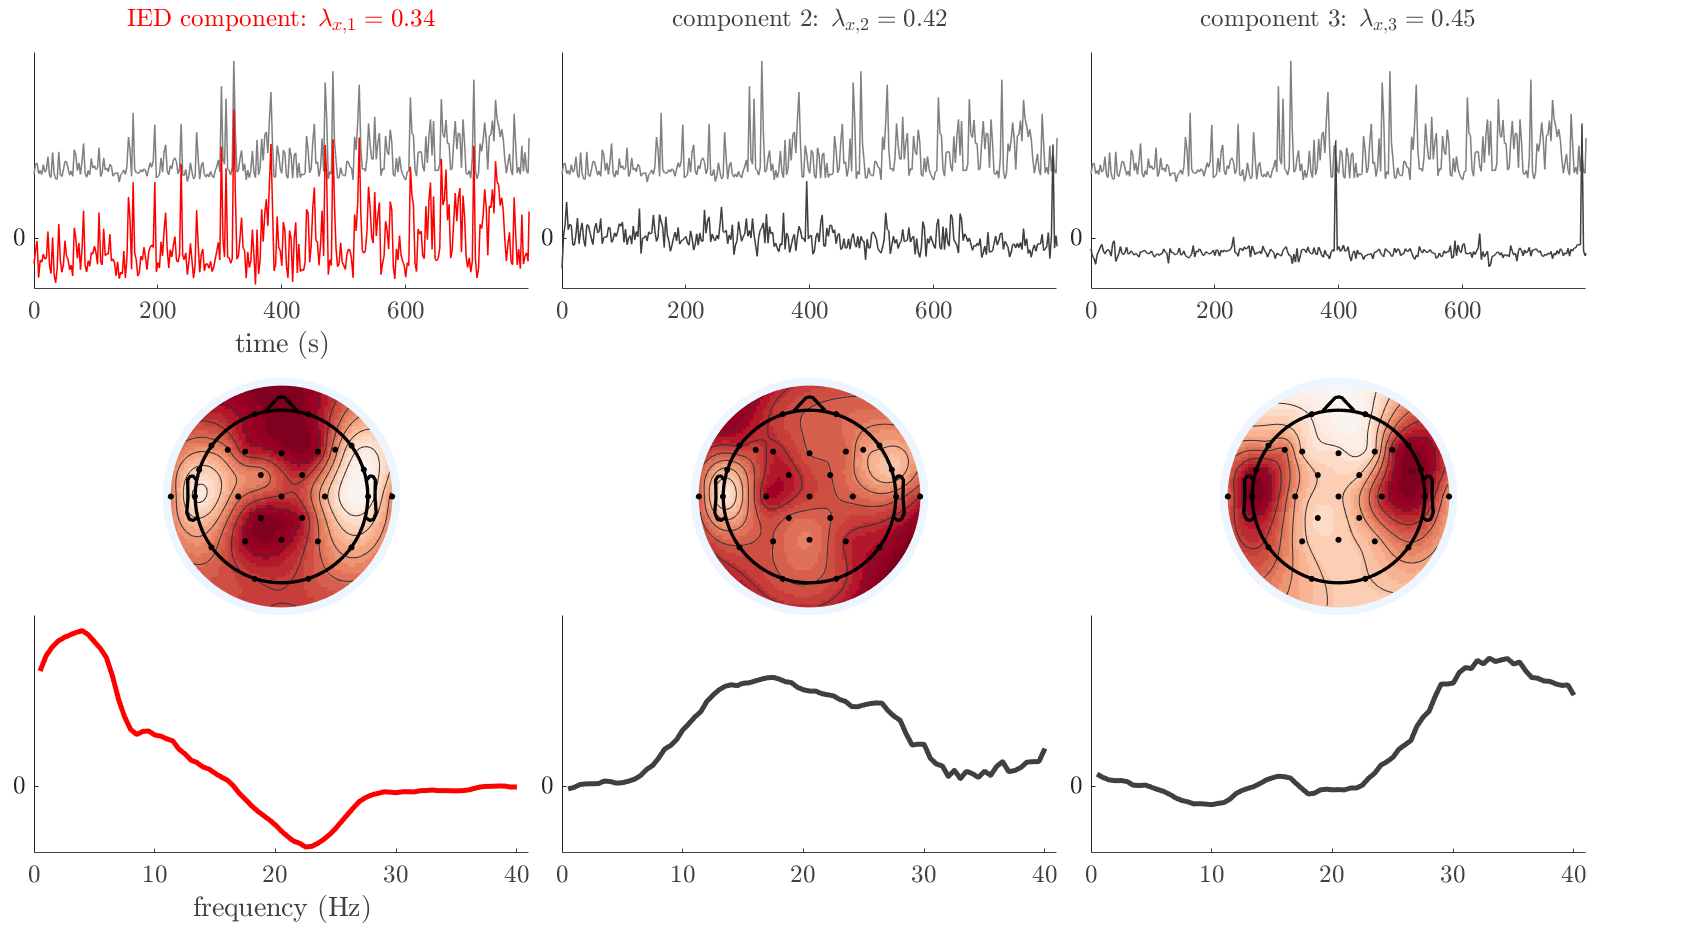

We analyze the solution with sources. Figure 1 shows the EEG signatures and HRF waveforms. One of the sources is highly correlated to the MWF reference (in grey), which was already known from Table B.3. This IED-related source had a typical low-frequency spectrum, which is expected for the typical spike-and-wave interictal discharges. The topography is relatively diffuse, although the highest amplitudes are mostly in the left hemisphere. This is in accordance with the lateralization of ictal onset zone (left temporal lobe, cfr. Table 1). There are some noteworthy observations to be made about some of the other components. The fourth has an unusually sharp spectrum, is mainly localized on two nonadjacent center electrodes, and is sustained for a single period of many seconds Hence, this component likely captured an artifact (of yet unknown origin), although we spotted no large-amplitude changes in the EEG itself. Similarly, the third source is only present at one frontal electrode, and exists in a frequency range above 20 Hz. It might represent a muscle artifact, e.g., due to frowning or twitching of some muscles in the forehead. The HRFs of all ROIs are shown in Figure 1(b). Two of the basis functions seem to have converged to a very similar waveform, which is an unfortunate possibility if two initial HRFs are too close to the same local optimum in their respective parameters. This reduces the expressive power of the basis set, which is clearly visible, since many ROIs have a nearly identical HRF. One of the twenty ROIs with the highest-entropy HRF overlapped the IOZ, although clearly this HRF (bold line) is not among the most dissimilar waveforms for this patient. This is also visible in Figure 2: both the HRF entropy and extremity maps show a small overlap with the delineated IOZ. Despite the good correspondence in the EEG domain, no significant (de)activation of the IED-component is found inside the IOZ.

We analyze the solution with sources, and show the results in Figure 3 and 4. As for patient 1, we found a source which is strongly correlated to the MWF envelope, and which had a mostly low-frequency behavior characteristic for spikes. The topography is mostly uninformative, and does not clearly correspond to the patient’s clinical data. The third source is mostly present at both sides of the head, is very sparsely active in time, and has a high-frequency content: this is most likely an artifact due to the neck muscles. Again, there is one of the highest-entropy HRFs which belongs to a ROI in the IOZ. Now, the waveform is clearly resolved from the other HRFs, through the strong initial dip (before 0 seconds). Such a dip is sometimes observed in HRFs, but its underlying physiological mechanism is not yet fully understood. It is possible that this dip reflects altered vascular autoregulation near the IOZ (cfr. the explanation in the Section 1 of the main text), or a rapid depletion in oxygen due to IED generation (before the IED becomes visible on the EEG). Figure 4 furthermore shows that the IED-related component is significantly active in parts of the IOZ, and deactive in others. As mentioned earlier, this deactivation may or may not be due to errors in sign correction. Interestingly, the ROI with the high alteration in neurovascular coupling is distinct from both the activated and deactivated ROIs.

We analyzed the solution with sources, and show the results in Figure 5 and 6. There is one source which is mostly correlated to the reference (but not extremely, see also Table B.3). This source had a right-temporal focus, conform the diagnosis in Table 1. The second source illustrates the phenomenon of an erroneous sign exchange between the spatial and spectral profiles. Also one of the HRFs has a negative polarity, which is a failure of the sign correction procedure (in this case, because there is exceptionally no positive overshoot). However, the HRF variability metrics are still interpretable, and indeed two ROIs among the ones with the highest-entropy HRFs overlap with the IOZ. The IED component is significantly active in a tiny portion of the IOZ (cfr. Figure 6). The second source is significantly active in symmetrical parts of the parietal lobe. Given its ongoing fluctuation over time, we hypothesize that this source captures a resting state network (RSN).

We analyze the solution with sources, and show the results in Figure 7 and 8. There is a clear IED-related component, with a very high correlation to the MWF reference, a typical spectrum, and an anterior-temporal focus, which corresponds very well to the patient’s diagnosis (cfr. Table 1). The fifth source seems present at only one channel, and has spectral harmonic at Hz and Hz. One of these peaks is reminiscent of the fourth component in patient 1. As Figure 8 shows, the HRF entropy and extremity prove to be strong biomarkers for the IOZ in this case, and also the significant IED activation and deactivation allow correct localization. In Figure 7, it is clear that some HRFs may still have the wrong sign, which means that the interpretation of ‘active’ and ‘deactivated’ is flipped in those ROIs. Hence, regions of significant deactivation are in fact significantly activated. The fourth source had a significant overlap with the auditory RSN, and its spectrum reveals activity in the band.

We analyze the solution with sources, and show the results in Figure 9 and 10. One source is strongly correlated to the MWF, while the other source is likely an artifact, given its very sparse temporal profile. Both sources coincide at one high-amplitude peak, by which we infer that this is probably an artifactual period in the signal. Indeed, when inspecting the original EEG signals, we found high-frequency muscle artifacts at these times. This source also had no significant activation in its spatial map, which corroborates its non-neuronal origin. The IED-related source had a broader spectrum than most other cases, and an uninformative topography. None of the ROIs with high-entropy HRFs is located in the IOZ. The pseudo t-map provides correct localization of the IOZ, however.

We analyze the solution with sources, and show the results in Figure 11 and 12. We found a clear IED-related component, with a characteristic spectrum and a topography which is backed up by the patient’s diagnosis (left anterior-temporal IOZ). The fourth source has a very similar topography and spectrum to the fifth source in patient 5. One HRF inside the IOZ had a high-entropy, and is distinguishable from the others by its very sluggish waveform, i.e., it is smeared out in time, with no sharp over- or undershoot. Also the pseudo t-map provided an accurate localization of the IOZ. Notably, in this patient, the extremity metric misses the deviating HRF in the IOZ (while the entropy metric picks it up). The second source overlapped with the frontal part of the default mode network (DMN), and is active in the and low bands.

We analyze the solution with sources, and show the results in Figure 13 and 14. We found two components which had correlated time courses. At the time of the peaks, we found higher-amplitude events in the EEG with dubious origin, hence they may or may not be artifacts. One of both components is more strongly correlated to the MWF, and its activation is concordant with the IOZ. The second component shows high overlap with the sensorimotor network. For this patient, none of the IOZ’s ROIs had extreme values of either HRF metric.

We analyze the solution with sources, and show the results in Figure 15 and 16. In this patient, there is only a moderate correlation of a component with the MWF reference time course. This component’s topography (left occipital) agrees with the clinical description, however. The HRF extremity (and not the entropy) is high in a small part of the IOZ. Both the significant IED activation and deactivation allow correct localization as well. The second source seemingly captured high-frequency oscillatory activity in the sensorimotor network, similar to the previous patient.

We analyze the solution with sources, and show the results in Figure 17 and 18. The IED-related source had a high correlation with the MWF reference, but an odd bimodal spectrum. Its EEG topography is very consistent with the clinical description. Both HRF extremity and entropy are useful biomarkers for the IOZ. The IED activation and deactivation maps each had a very small overlap with the IOZ. The second source is temporally sparse and captures high-frequency EEG variations, which we identified as muscle artifacts.

We analyze the solution with sources, and show the results in Figure 19 and 20. Again we observe an IED-related source and a seemingly artifactual source with a spectral peak near 34 Hz. Many of the high-entropy HRFs are highly noncausal, and are associated to ROIs inside the IOZ. Hence, with both HRF metrics, the highest-scoring ROIs provides good localization of the HRF. While there are no significantly active ROIs in the IOZ, there are several significantly deactivated ROIs, which may indicate that the sign standardization was not done flawlessly (cfr. also some of the negative-peaking HRFs for patient 10). Surprisingly, the second source had one significantly active ROI, which overlaps with the IOZ, but which did not match its EEG topography. Hence, the nature of this source remains ambiguous.